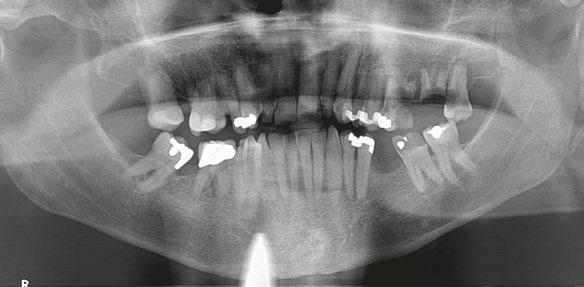

The patient returned a year later in December 2019 after receiving bilateral knee replacements. He wanted to fully recover and rehab from the knee reconstructive surgery before having his dental implants placed. A panoramic radiograph and CBCT were performed with Carestream CS9300 (Carestream

13 implantpracticeus.com Volume 16 Number 1 TECHNIQUE

Figure 5: Panoramic radiograph taken after healing of the grafted areas prior to implant placement Figure 6: CBCT taken after healing of the grafted areas prior to implant placement Figure 2: Placing the PRF and cortical cancellous bone preparation “sticky bone” into the extraction sockets Figures 3 and 4: 3. Double-layer PRF membrane placed underneath the buccal and palatal flaps prior to closure. 4. 3-0 PTFE suture used to provide closure of the buccal and palatal flaps and stability of the PRF membrane. Notice here primary closure is not necessary. This technique will provide a large band of keratinized tissue for use during implant placement

Atlanta, Georgia) (Figures 5 and 6). The patient was taken to the oral surgical suite where a 23-gauge butterfly intravenous catheter was started in the right antecubital fossa, and anesthesia was maintained thereafter with a balance technique. A crestal incision was performed, and a full-thickness flap was reflected. Osteotomies were performed using appropriate drills. A BioHorizons Tapered Pro 4.2 mm x 12 mm implant was placed at tooth No. 14 position, and a BioHorizons Tapered Pro 5.2 mm x 10.5 mm implant was placed at tooth No. 15 area. Both implants were placed with greater than 35 ncm torque values (Figure 7). Gingival former healing collars were placed for single stage implant surgery. The wound was closed using interrupted sutures, and the patient was discharged in the care of a family member.

One can appreciate the decrease in bone density in the ungrafted posterior maxilla (Figure 8) and the moderately more dense appearance in the grafted site where the PRF graft changed the local topography (Figure 9). The implants have subsequently integrated, and the patient is waiting to return to the restorative dentist when “he feels comfortable returning to a dentist office post-COVID” for a planned splinted cement-retained restoration. In the posterior maxillary region, this restoration would allow a greater chance of success in the D3 bone.

Figure 7: Postoperative periapical radiograph immediately after implant placement Figure 8: Notice the lack of bone density in the ungrafted maxillary left third molar socket Figure 9: The PRF/cortical cancellous bone graft increased the density of the implant site as seen in the postoperative transaxial CBCT view